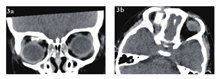

急诊入院者16例,6例患者行了MRI检查,主要为CT发现絮状密度影等感染征象、未发现异物影的,2例MRI发现异物影(图4a~d)。早期入院者7例,5例行了MRI检查(包括3例CT未发现异物的患者),其中3例发现异物影。其主要表现为:T1WI呈等信号或低信号,T2WI呈等信号,增强时中央无强化影,周边强化(图5a~d);中晚期入院者19例,16例行了眼眶MRI检查(未行MRI检查的为CT明确发现异物的)。其中15例患者发现异物影(93.8%),主要表现为:T1WI呈低信号,T2WI呈等信号或混杂高信号表现,增强时多表现为病灶中央无强化影(异物,不强化),周边明显强化(冠状位的典型表现为环状增强)(图6a~d)。